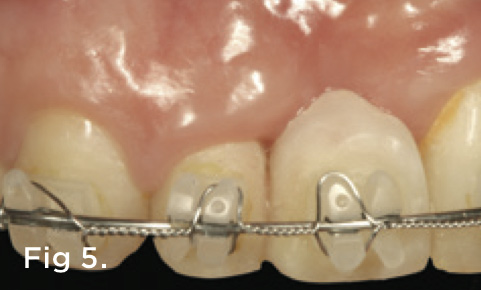

Fig 2. Radiograph showing the loss of periodontal attachment on the mesial aspect of tooth No. 7. A bone graft was placed when the implant was removed.

Figure 2

Fig 5. After completed forced eruption, tooth No. 7 was stabilized for 6 months. All the pink acrylic was eventually removed and the mesial papilla was now coincident with that of tooth No. 9.

Figure 5